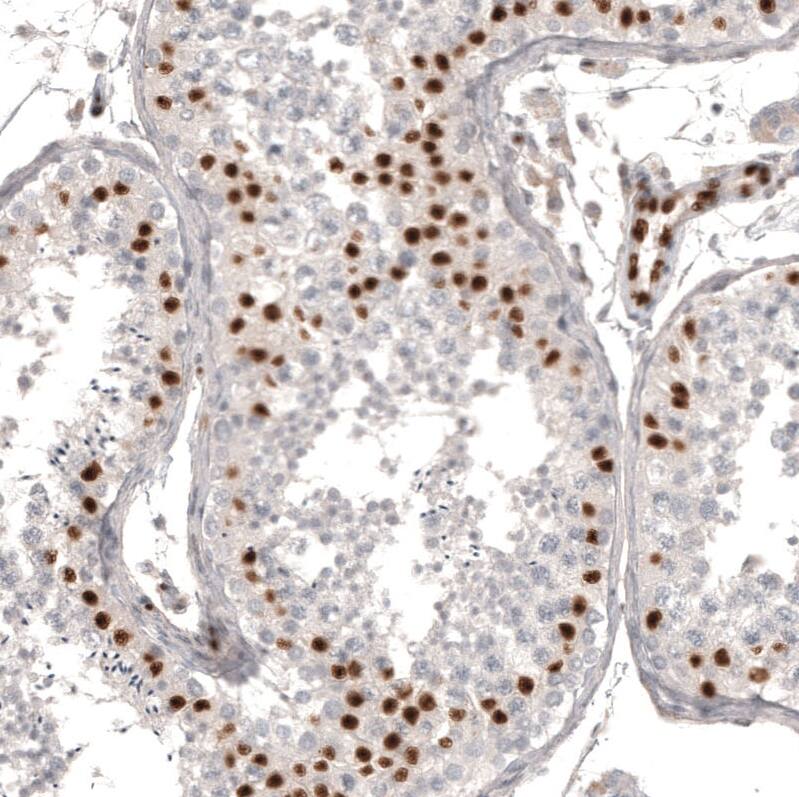

Staining of human testis shows strong nuclear positivity in cells in seminiferous ducts.